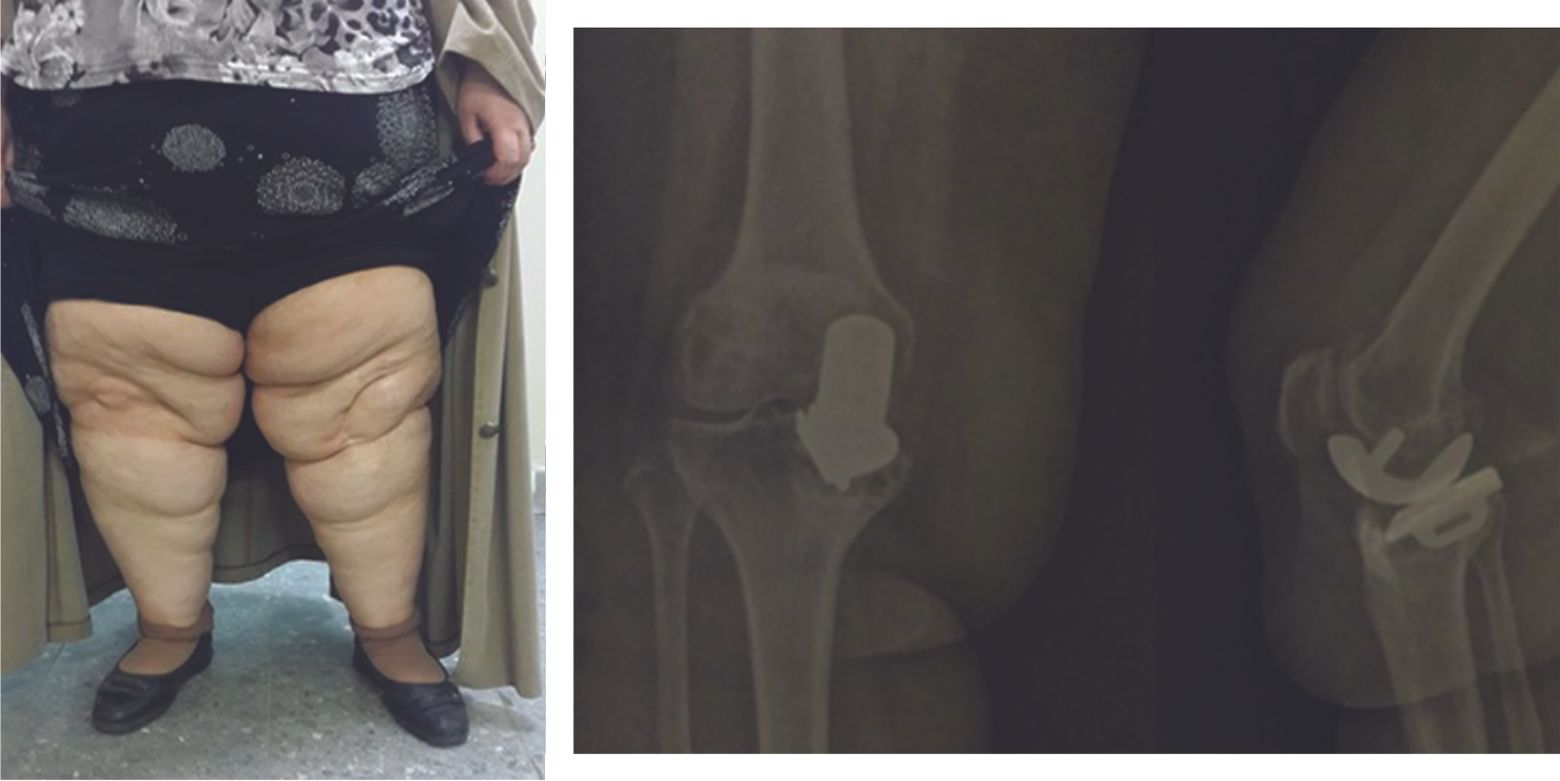

Morbid obesity is however a contraindication since it generally carries a higher rate of revision (Figs. 2 and 3).21

In conclusion, obesity is not a limit, but care should be taken in cases of morbid obesity (BMI > 35).

A meticulous technique is especially important in these patients since any positioning errors will soon make themselves felt.